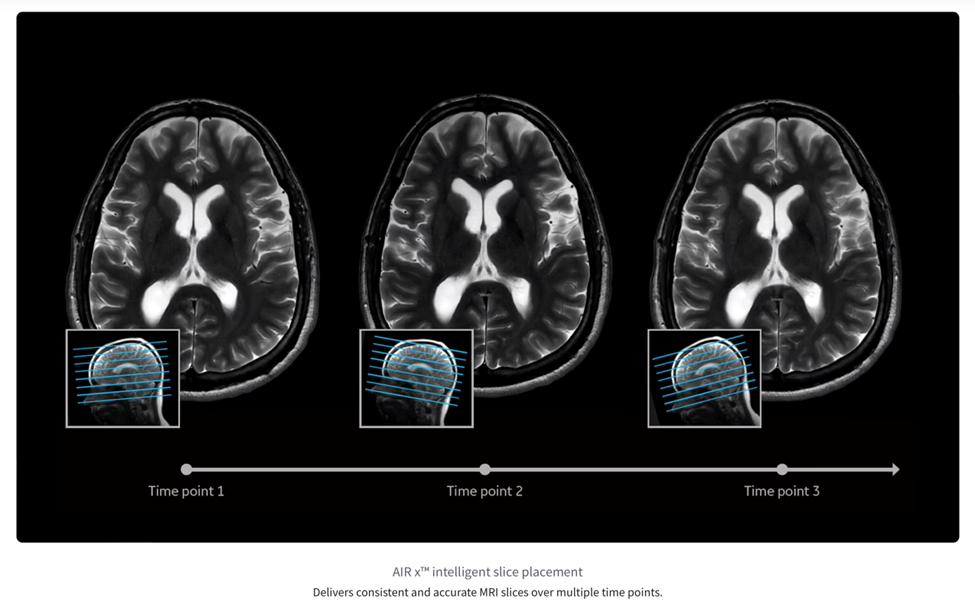

1. AIRx Suite: Automating MRI Slice Prescription

AIRx is a software tool that analyzes the three‑plane “localizer” scan taken at the very beginning of an MRI exam and then automatically chooses the MRI slices—thin, cross‑sectional pictures of the body—that an experienced technologist would normally set up by hand. The underlying deep-learning model powering AIRx was trained on tens of thousands of images, and detects patient anatomy with sufficient accuracy to hold slice-to-slice angular error below two degrees across neurological and knee protocols.

In practice this reduces a typical 95-click prescription workflow to just two confirmation clicks. Shorter table times ease claustrophobia for patients and free technologists to spend more time interacting with patients, while perfectly aligned follow-up studies give radiologists clear side-by-side comparisons that improve the detection of subtle disease progression.